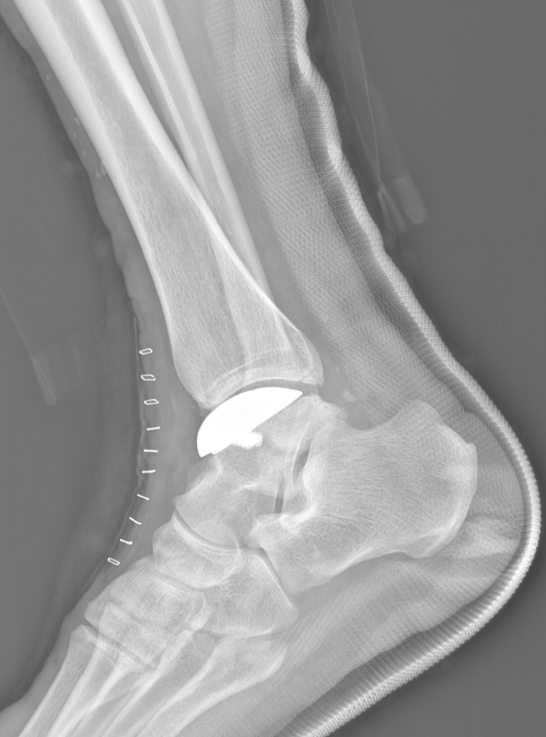

武勇主任团队给他做了3D打印导板辅助下人工全踝关节置换术。

这种手术适合踝关节病严重的患者,通过替换病变的关节结构,能帮着缓解疼痛、恢复关节活动,让老人日常走路更自在些。

术后侧位X线

术后正位X线